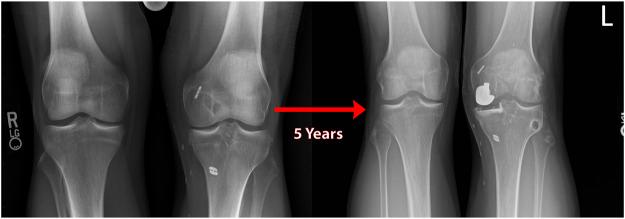

Posterior medial meniscus root tears (PMMRTs) make up a relatively notable proportion of all meniscus pathology and have been definitively linked to the progression of osteoarthritis (OA). While known risk factors for development of OA in the knee include abnormal tibial coronal alignment, obesity and female gender, PMMRTs have emerged in recent years as another significant driver of degenerative disease. These injuries lead to an increase in average contact pressure in the medial compartment, along with increases in peak contact pressure and a decrease in contact area relative to the intact state. Loss of the root attachment impairs the function of the entire meniscus and leads to meniscal extrusion, thus impairing the force-dissipating role of the meniscus. Anatomic meniscus root repairs with a transtibial pullout technique have been shown biomechanically to restore mean and peak contact pressures in the medial compartment. However, nonanatomic root repairs have been reported to be ineffective at restoring joint pressures back to normal. Meniscal extrusion is often a consequence of nonanatomic repair and is correlated with progression of OA. In this study, the authors will describe the biomechanical basis of the natural history of medial meniscal root tears and will support the biomechanical studies with a case series including patients that either underwent non-operative treatment (5 patients) or non-anatomic repair of their medial meniscal root tears (6 patients). Using measurements derived from axial MRI, the authors will detail the distance from native root attachment center of the non-anatomic tunnels and discuss the ongoing symptoms of those patients. Imaging and OA progression among patients who were treated nonoperatively before presentation to the authors will be discussed as well. The case series thus presented will illustrate the natural history of meniscal root tears, the consequences of non-anatomic repair, and the findings of symptomatic meniscal extrusion associated with a non-anatomic repair position of the meniscus.

后内侧半月板根部撕裂(PMMRTs)在所有半月板病变中占比较显著,并且已明确与骨关节炎(OA)的进展相关。虽然已知膝关节OA发展的风险因素包括胫骨冠状面排列异常、肥胖和女性性别,但近年来PMMRTs已成为退行性疾病的另一个重要驱动因素。这些损伤导致内侧间室平均接触压力增加,同时峰值接触压力增加,且相对于完整状态接触面积减小。根部附着的丧失会损害整个半月板的功能,并导致半月板挤出,从而损害半月板的力消散作用。经胫骨拉出技术进行的解剖学半月板根部修复在生物力学上已显示可恢复内侧间室的平均和峰值接触压力。然而,据报道非解剖学根部修复在将关节压力恢复到正常水平方面无效。半月板挤出通常是非解剖学修复的结果,并且与OA的进展相关。在本研究中,作者将描述内侧半月板根部撕裂自然病程的生物力学基础,并将通过一个病例系列来支持生物力学研究,该病例系列包括接受非手术治疗的患者(5例)或内侧半月板根部撕裂接受非解剖学修复的患者(6例)。作者将使用从轴向MRI得出的测量值,详细说明非解剖学隧道与天然根部附着中心的距离,并讨论这些患者的持续症状。还将讨论在向作者就诊之前接受非手术治疗的患者的影像学和OA进展情况。因此呈现的病例系列将说明半月板根部撕裂的自然病程、非解剖学修复的后果以及与半月板非解剖学修复位置相关的有症状半月板挤出的发现。